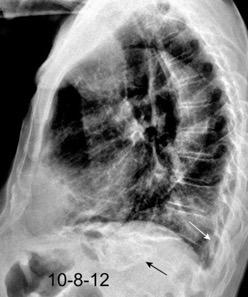

Tromboembolismo pulmonar Diafragma elevado 20%

Consolidación por Infarto pulmonar. (TEP)

Visible en 2/3 posteriores

El corazón borra el1/3 anterior

Atelectasia crónica de LLI en paciente con enfermedad neuromuscular.